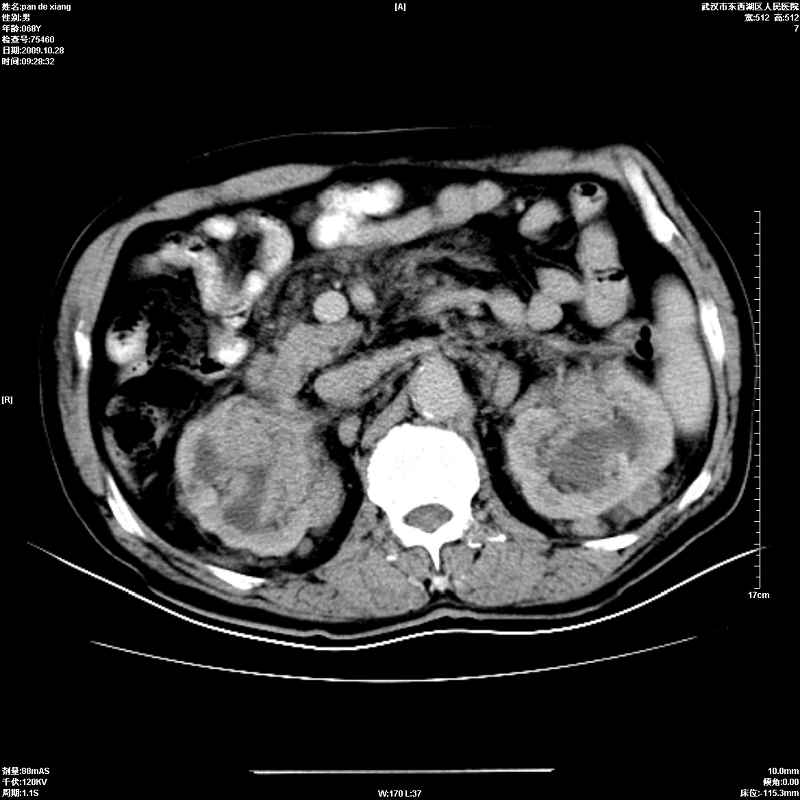

以下是引用杀毒软件在2009-10-28 20:41:00的发言:[br]结合临床考虑---白血病双肾改变或淋巴瘤。

以下是引用zxl51642在2009-10-29 9:59:00的发言:[br]结合临床“单克隆免疫球蛋白血症”,考虑双肾为继发损害并肾功能不全(尿中大量igg及少量iga、igm等大分子免疫球蛋白滤出所致继发损害),椎前软组织肿块为髓外造血。与浆细胞瘤有区别,平扫时有战友说的很清楚。